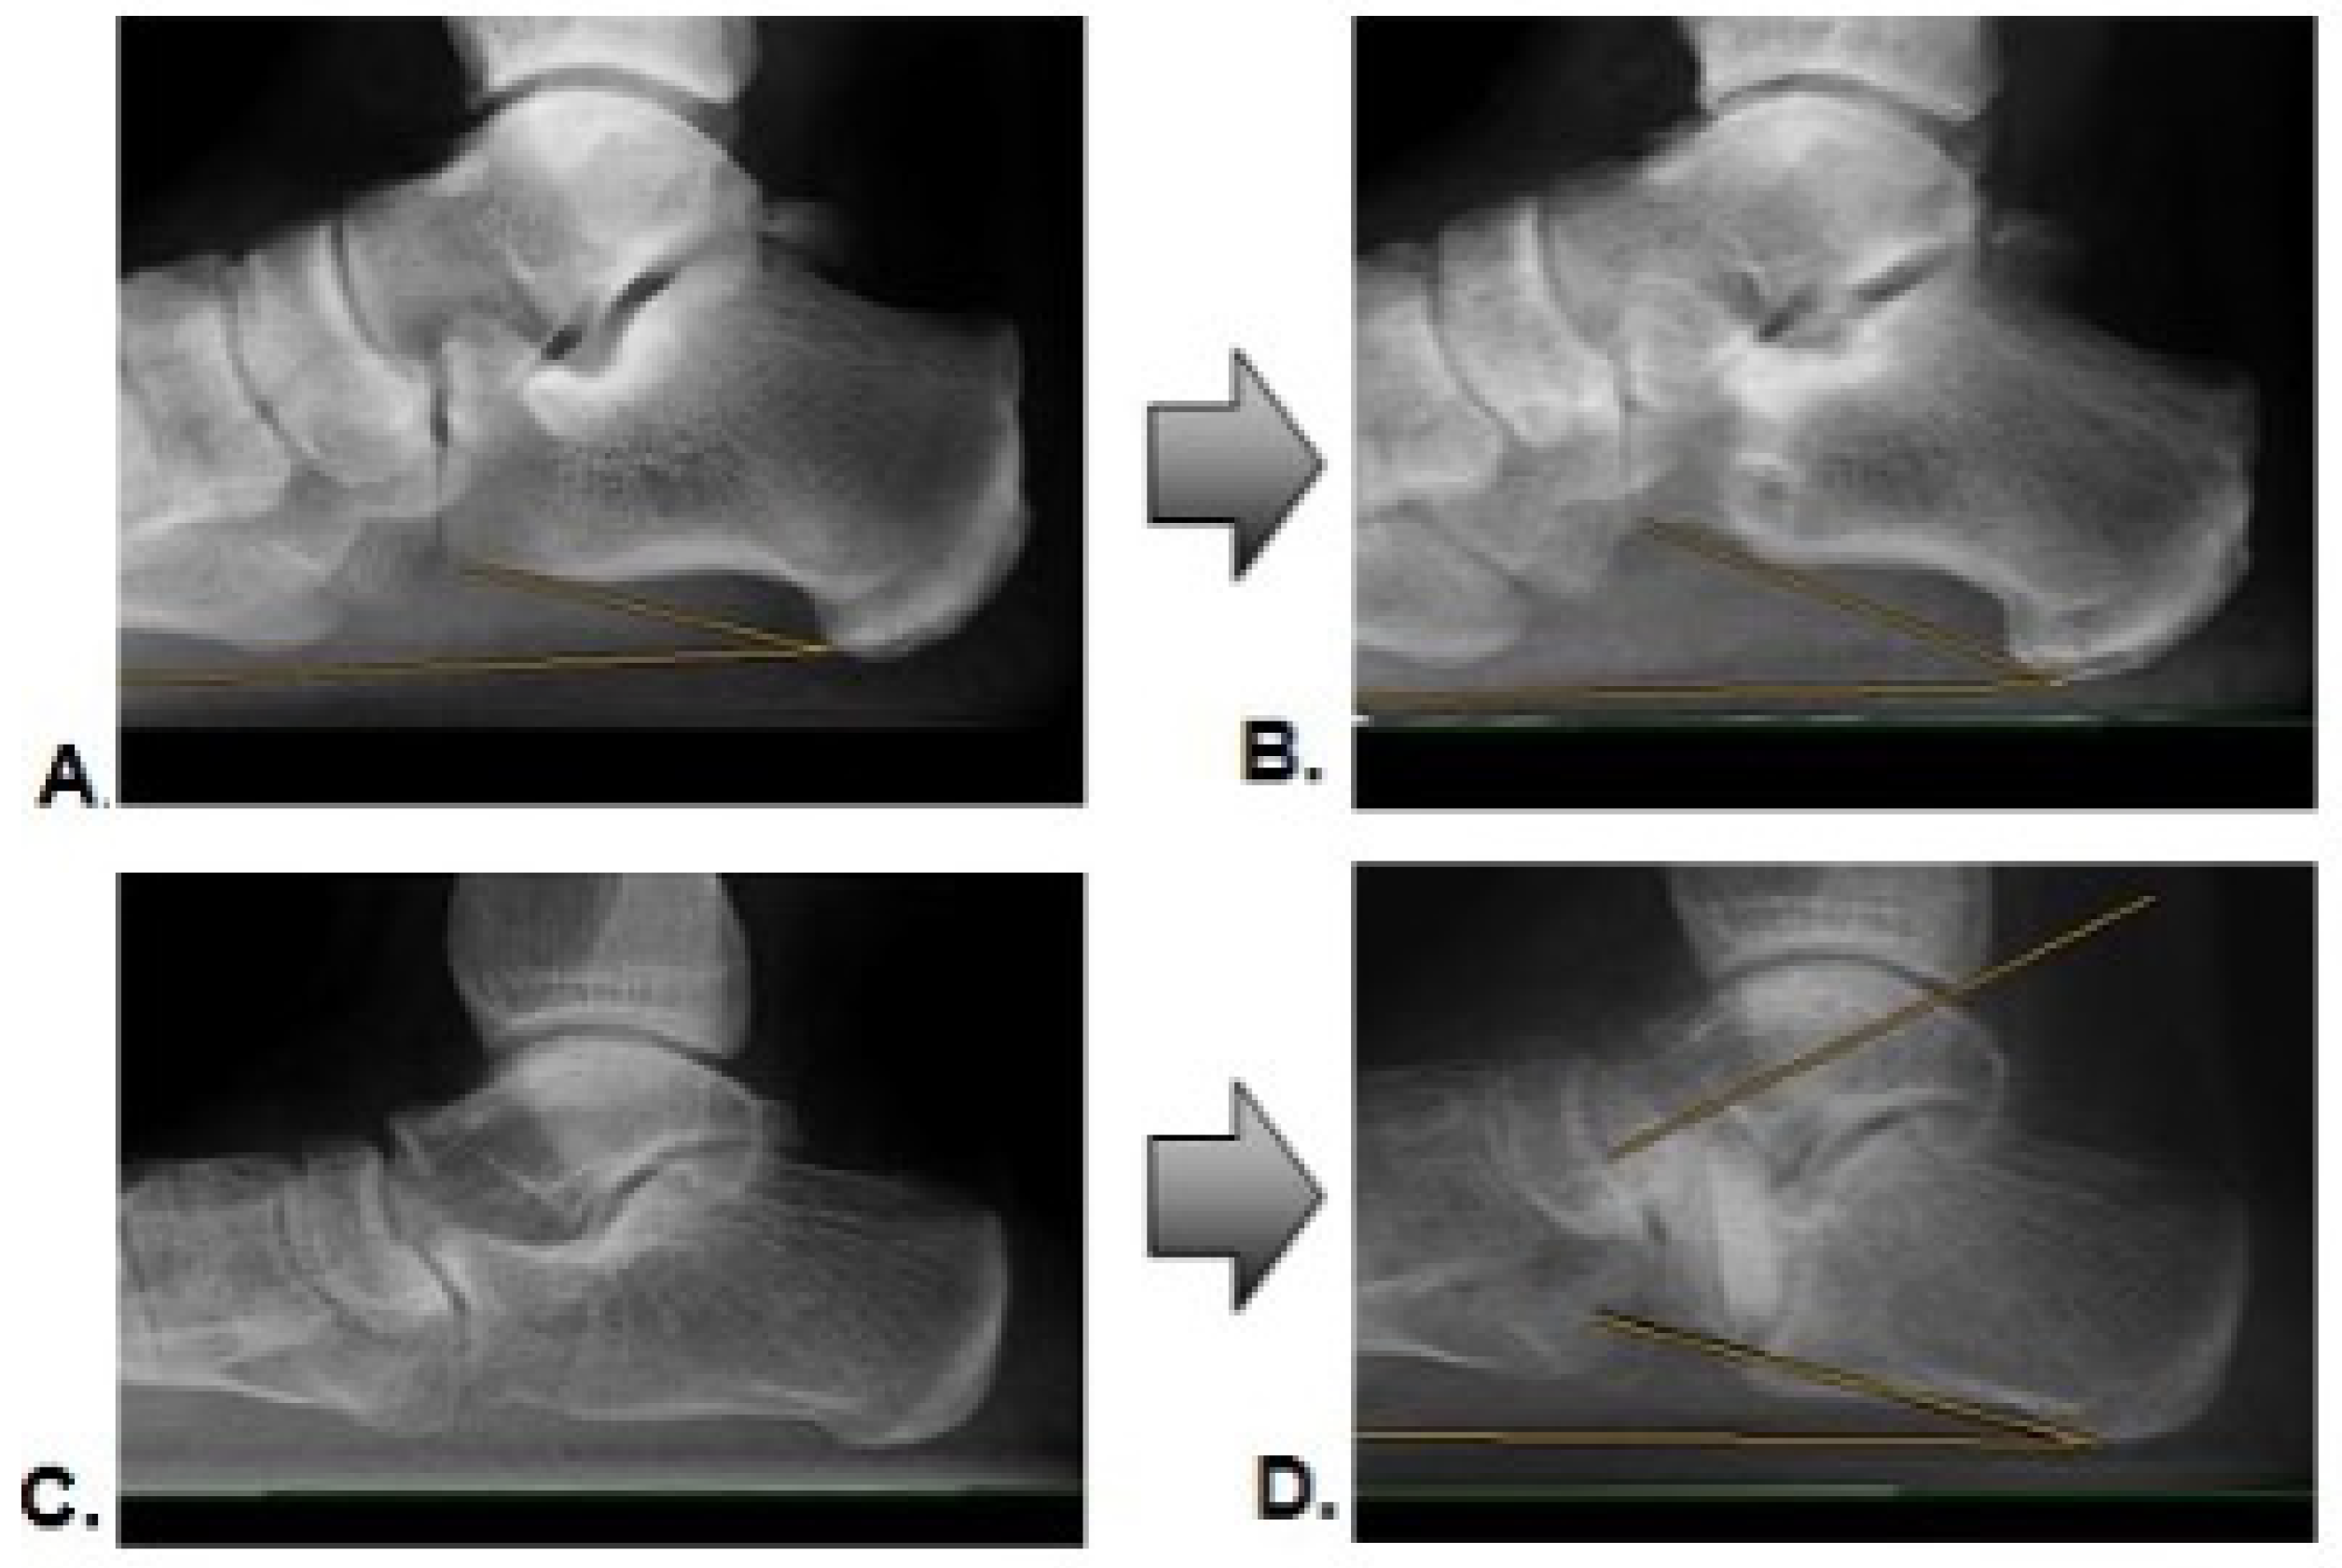

As part of the six-month postoperative clinical follow-up, native weight-bearing radiological imaging was conducted. The radiologically determined incorporation of the bone graft was evaluated according to the criteria of Worth et al. (see Figure 2) by two independent, blinded investigators [20]. Grades III and IV were considered successful incorporation.

3.3. Incorporation Rate

Within six months of the postoperative follow-up, the AG showed a successful incorporation of the transplanted autologous bone grafts in 26 transplants (96.3%). Only one transplant failed to demonstrate sufficient consolidation (3.7%). For the XG at a six-month follow-up, nine transplants (57%) were incorporated. Seven bone grafts (43%) showed grade I or II, according to Worth et al. [20]. Figure 3 gives an example of a successful incorporation (Figure 3A,B) and an example of a failed incorporation with a loss of correction (Figure 3C,D).

Figure 3. Radiographic example of pre- and postoperative images with successful incorporation (A,B), and loss of correction with incomplete incorporation (C,D).